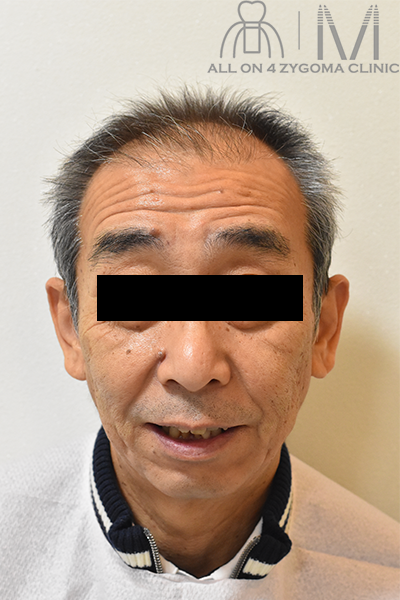

左:初診時

術前顔貌所見

顔貌は左右非対称、右口角の位置が左口角の位置より高位にある。鼻唇溝は深く、右側で著明。鼻翼の位置は両側ほぼ対称。

上唇が薄く、下唇が厚い。

笑顔時に上唇から見える上顎前歯部は歯冠部の1/3部が露出

バッカルコリドーは写真では認めるようだが不明瞭。